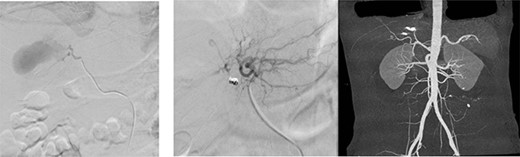

Embolization was achieved using gel foam and particle (embosphere: 100–300 mic) through microcatheter until satisfactory stagnation of forward flow was reached and back flow was seen. Then, the aneurysm was occluded with placement of six microcoils (3 and 5 mm) (Fig. 6).

(a) Arteriogram showing a hepatic artery pseudoaneurysm in the right hepatic artery; (b) shows post-embolization selective arteriogram showing disappearance of the pseudoaneurysm in the right lobe of the liver; CT angiogram shows successful embolization (c).